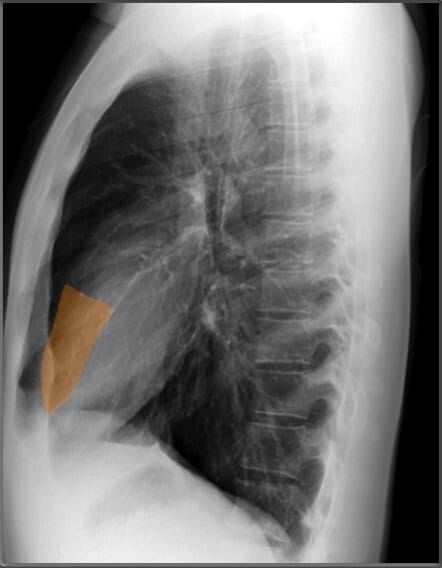

| 늑골횡격막각 (Costophrenic Angle) |

| ✅ 늑골과 횡격막이 만나는 각도로, 정상적으로 뚜렷하고 예리하게 보여야 합니다. 둔해지거나 소실되면 흉수(pleural effusion) 가능성을 시사합니다. |